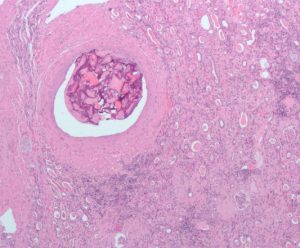

1.In Exercise 1, you observed normal capillary, artery and vein structure. Below you have a diseased artery in the kidney (Figure 20.12).

Figure 20.12 Cross section of a diseased artery in the kidney. (Credit: Wikipedia, Nephron. CC-BY-SA3 license)

Compare and contrast the structure of this artery with the normal artery you observed.

• List the similarities between this diseased artery and the normal artery features you observed.

• List what is different in this artery compared to the normal artery you observed.

• What effect would you expect this artery problem to have on blood flow? Blood pressure? Explain.